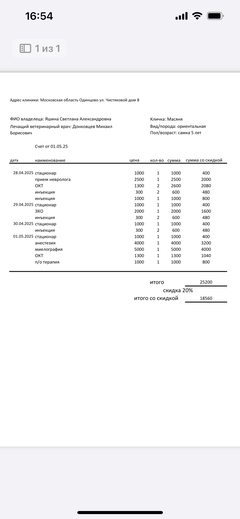

Была куплена в питомнике взрослой. У Масяни начались проблемы с кишечником и она стала подтекать и все пачкать. Надо отдать должное хозяевам - ее обследовали вдоль и поперек - как говорили местные врачи, сдавали много анализов но диагноза так и не поставили.

Ярко выраженная болезненность в области крестца, на обезболе полегче. По результатам приема невролога проведена миелография - множественная компрессия, возможно опухоль, возможно грыжа, нужно удалять...